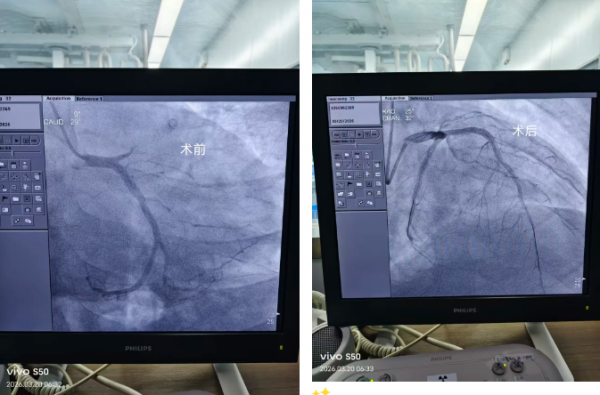

我院在院前接诊阶段便已启动急诊绿色通道,依托胸痛中心快速响应机制,待患者生命体征稍稳后,各相关科室高效联动,无缝衔接急诊抢救室与导管室,快速护送患者接受急诊血管介入治疗。内五科团队精准研判、娴熟操作,迅速开通堵塞血管、恢复心肌供血,牢牢把握救治关键时机。